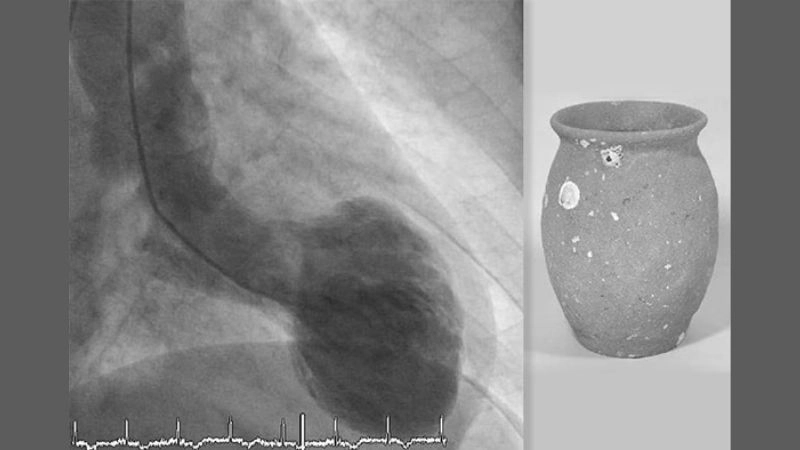

Images visual examples of Takotsubo Cardiomyopathy (Broken Heart Syndrome)

Visual examples of Takotsubo Cardiomyopathy (Broken Heart Syndrome) often display the heart’s left ventricle ballooning into a distinctive shape, reflecting weakened muscle contraction caused by sudden stress.